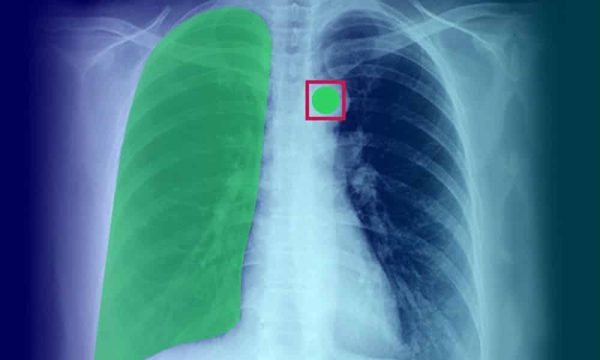

Cancer Detection

Cancer cell detection is perhaps the biggest role of AI in medical imaging analysis. When models are trained on massive sets of medical imaging data, it helps the model accurately identify, detect and predict the growth of cancer cells in organs. As a result, the potential for human errors and false positives can be eliminated to a large extent.